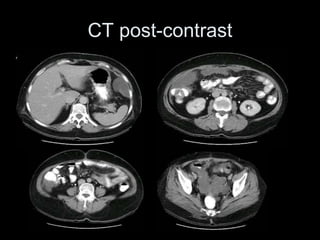

Pseudomyxoma peritonei (PMP) is a rare condition characterized by gelatinous ascites resulting from the rupture of appendiceal mucinous tumors, leading to significant abdominal complications. The incidence is approximately 2 cases per million per year, with a predominance in females, and diagnosis often relies on imaging techniques like ultrasound and CT scans. Effective treatment involves cytoreductive surgery combined with hyperthermic intraperitoneal chemotherapy (HIPEC) to manage disease progression and improve outcomes.